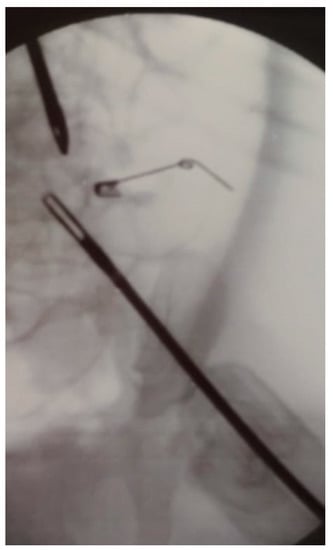

7. Brachytherapy and Abdominal Surgery

- Komasara, L.; Gołębiewski, A.; Anzelewicz, S.; Czauderna, P. A review on surgical techniques and organ sparing procedures in bladder/prostate rhabdomyosarcoma. Eur. J. Pediatr. Surg. 2014, 24, 467–473. [Google Scholar] [CrossRef]

- Heinzelmann, F.; Thorwarth, D.; Lamprecht, U.; Kaulich, T.W.; Fuchs, J.; Seitz, G.; Ebinger, M.; Handgretinger, R.; Bamberg, M.; Weinmann, M. Comparison of different adjuvant radiotherapy approaches in childhood bladder/prostate rhabdomyosarcoma treated with conservative surgery. Strahlenther. Onkol. 2011, 187, 715–721. [Google Scholar] [CrossRef]

- Castagnetti, M.; Herbst, K.W.; Esposito, C. Current treatment of pediatric bladder and prostate rhabdomyosarcoma (bladder preserving vs. radical cystectomy). Curr. Opin. Urol. 2019, 29, 487–492. [Google Scholar] [CrossRef] [PubMed]

- Fuchs, J.; Paulsen, F.; Bleif, M.; Lamprecht, U.; Weidner, N.; Zips, D.; Neunhoeffer, F.; Seitz, G. Conservative surgery with combined high dose rate brachytherapy for patients suffering from genitourinary and perianal rhabdomyosarcoma. Radiother. Oncol. J. Eur. Soc. Ther. Radiol. Oncol. 2016, 121, 262–267. [Google Scholar] [CrossRef]

- Michel, J.; Sauter, L.; Neunhoeffer, F.; Hofbeck, M.; Kumpf, M.; Paulsen, F.; Schmidt, A.; Fuchs, J. Sedation practices during high dose rate brachytherapy for children with urogenital and perianal Rhabdomyosarcoma. J. Pediatr. Surg. 2020, in press. [Google Scholar] [CrossRef] [PubMed]

- Chargari, C.; Haie-Meder, C.; Guérin, F.; Minard-Colin, V.; de Lambert, G.; Mazeron, R.; Escande, A.; Marsolat, F.; Dumas, I.; Deutsch, E.; et al. Brachytherapy Combined With Surgery for Conservative Treatment of Children With Bladder Neck and/or Prostate Rhabdomyosarcoma. Int. J. Radiat. Oncol. Biol. Phys. 2017, 98, 352–359. [Google Scholar] [CrossRef]

- Martelli, H.; Borrego, P.; Guérin, F.; Boubnova, J.; Minard-Colin, V.; Dumas, I.; Chargari, C.; Haie-Meder, C. Quality of life and functional outcome of male patients with bladder-prostate rhabdomyosarcoma treated with conservative surgery and brachytherapy during childhood. Brachytherapy 2016, 15, 306–311. [Google Scholar] [CrossRef]